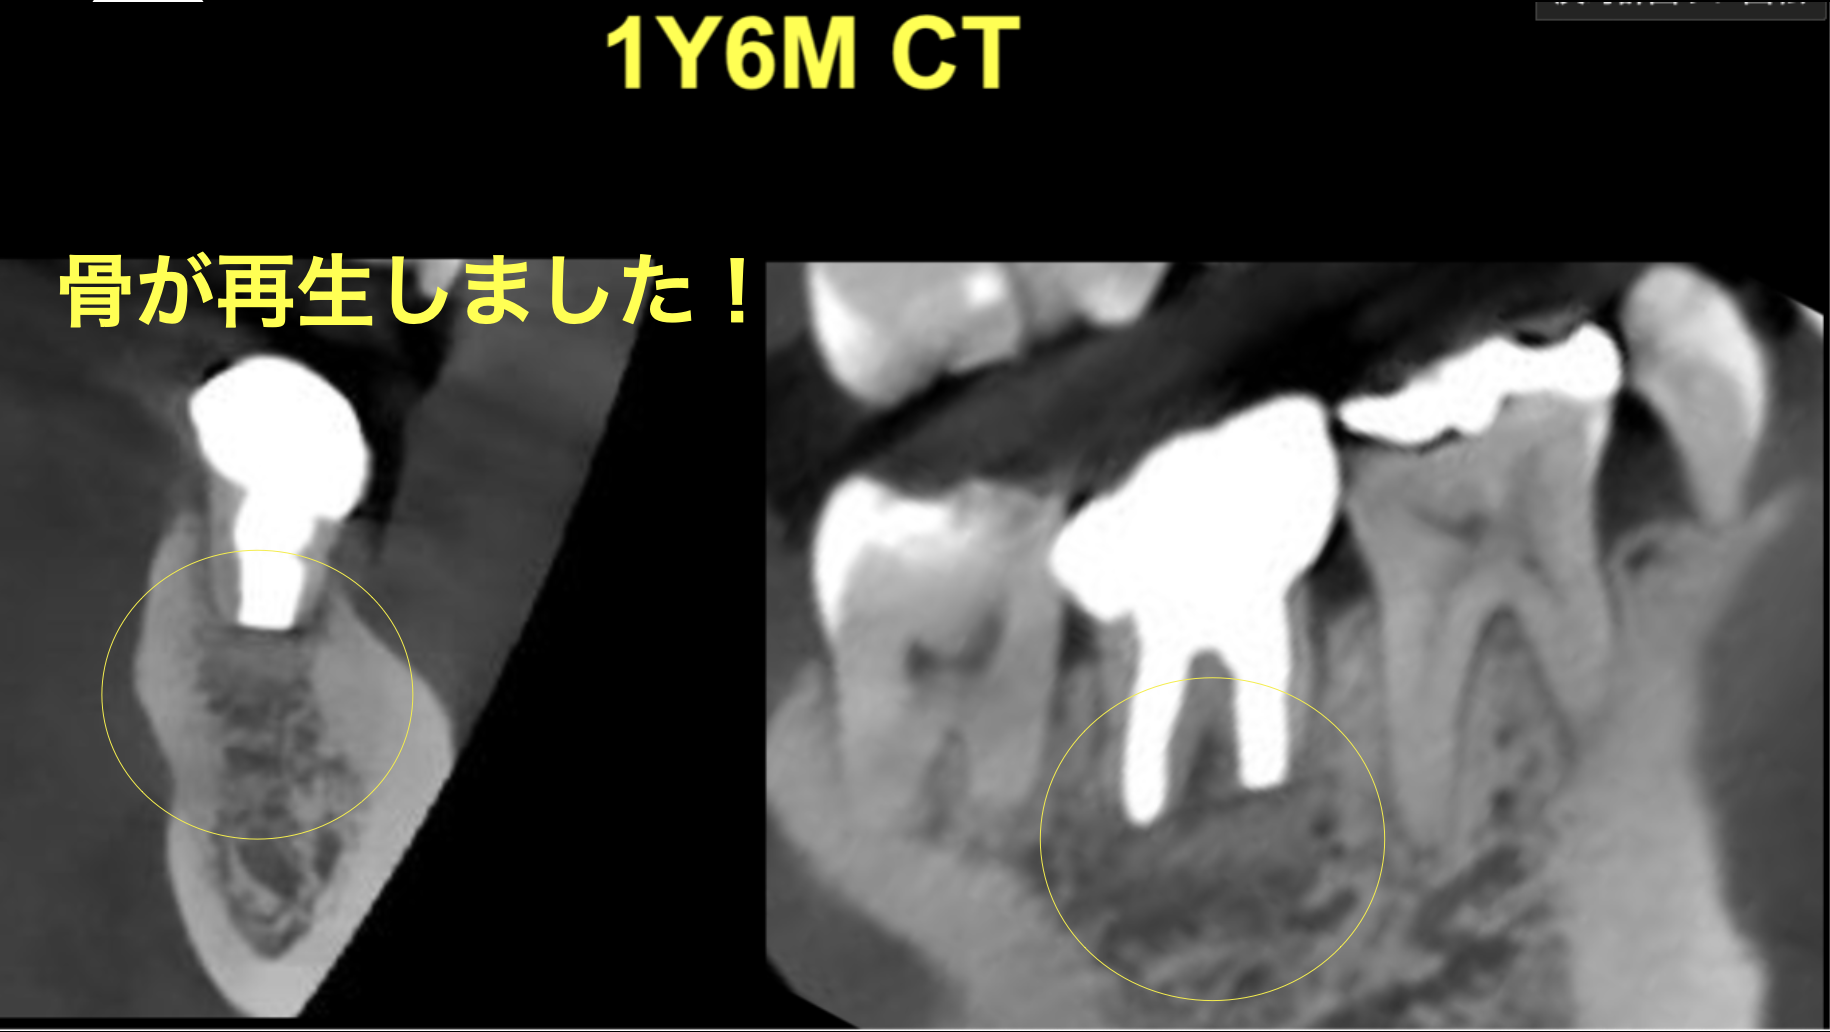

意図的再植術 1年6ヶ月後の経過

治療後

| 治療の方法 | 意図的再植術 |